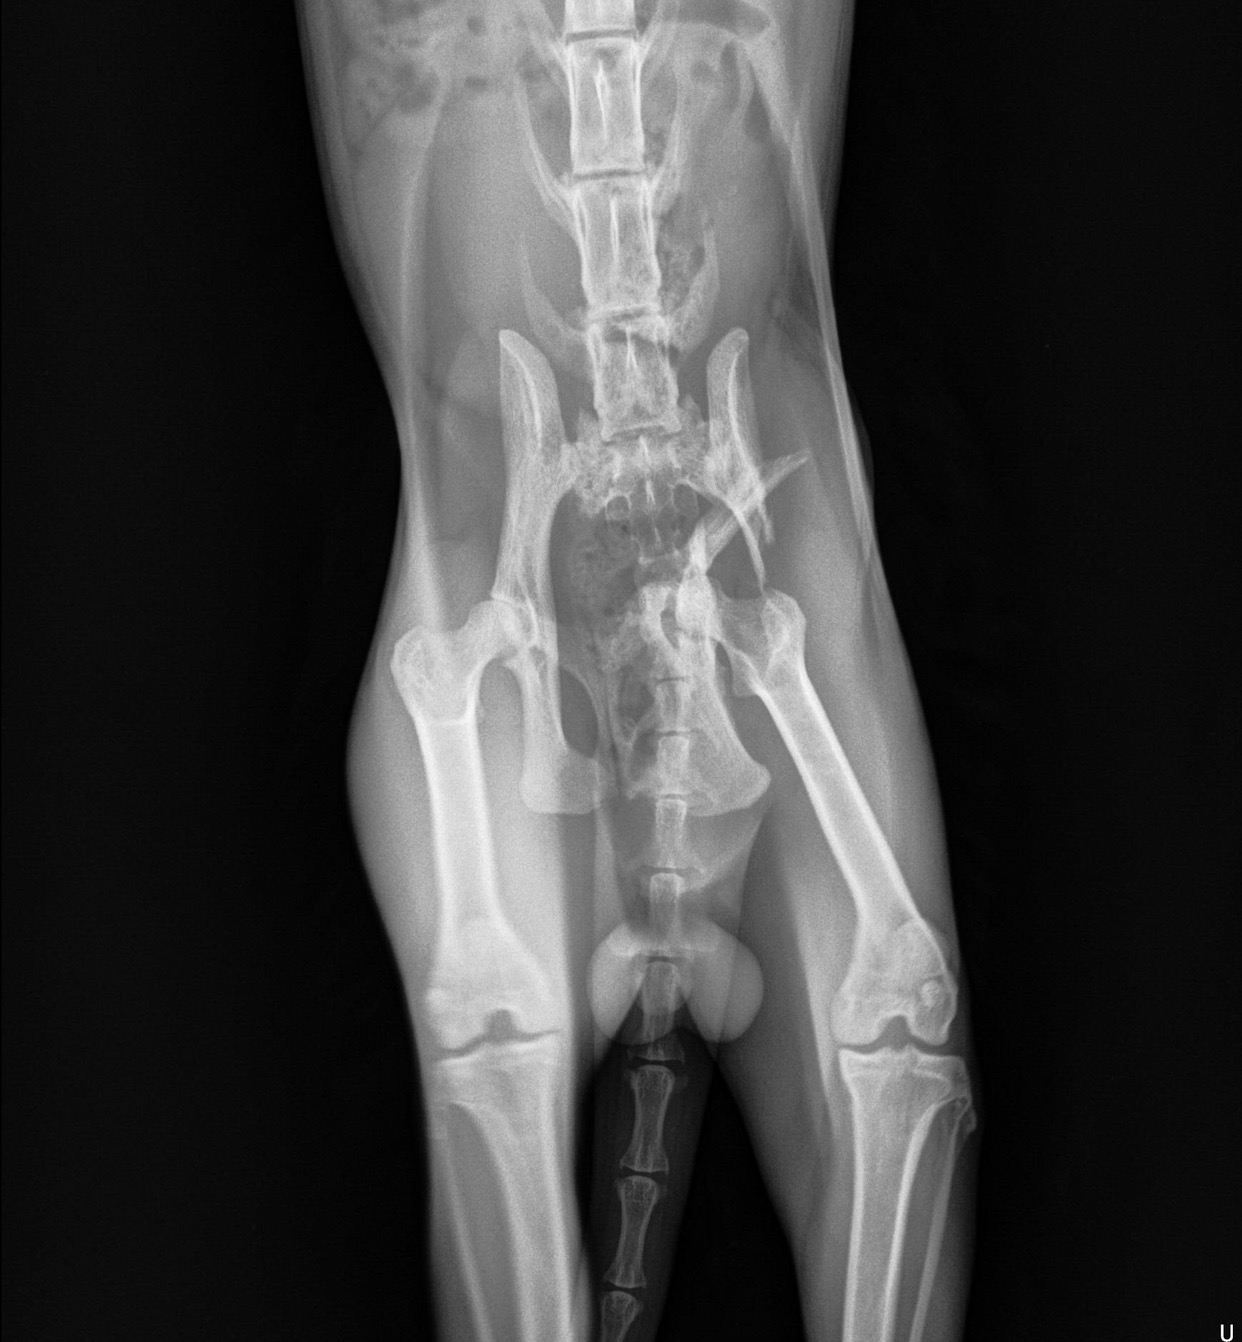

He can’t put any weight on his left hind leg, and even at the pelvis his leg looks misaligned. I’m already anticipating he will need at the very least an X-ray and a cast, maybe a surgery and medicine. I need help raising funds in anticipation of what I’m sure will be a high vet bill.